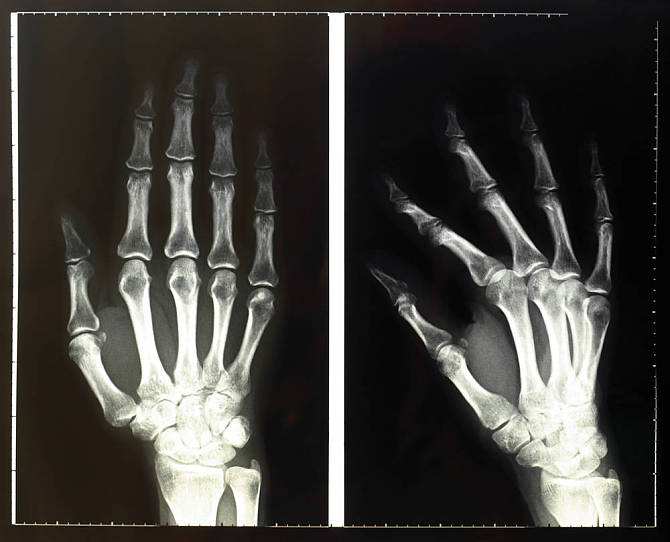

医生在进行X射线摄片时,将能感光的底片放在人体下方。当X射线透过人体时,骨骼、牙齿等组织内含有的钙质会吸收部分的射线,使到达底片的X射线减少,这样就能在底片上留下组织的影子了。这就像阳光下人的影子一样。人类第一幅X线片就是德国大科学家伦琴为他夫人所拍的手骨特写。其实不光是骨骼,其他凡是能够吸收X射线的物体,都会在感光底片上留下它们的身影。X射线就是这样一种神奇的射线。